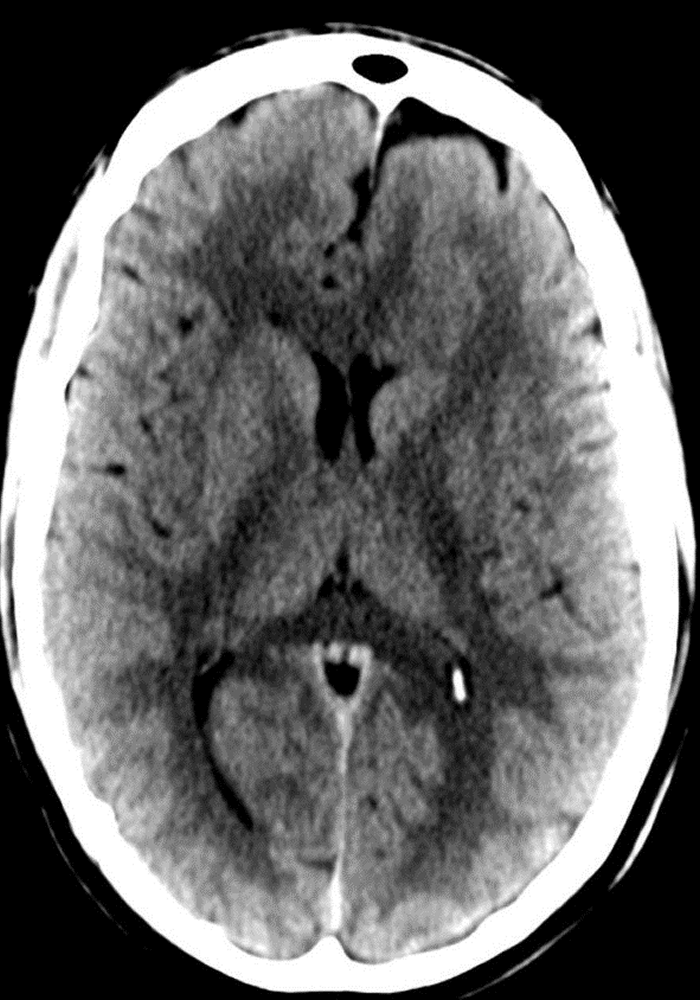

Before: "fuzzy" head CT

datascientists after

After: detailed images

Our V Star computer scientists wrote a module for 3D-Slicer allowing careful alignment and summation from 8 prior CT scans obtained over a course of several years. This improved image contrast resolution without loss of spatial resolution